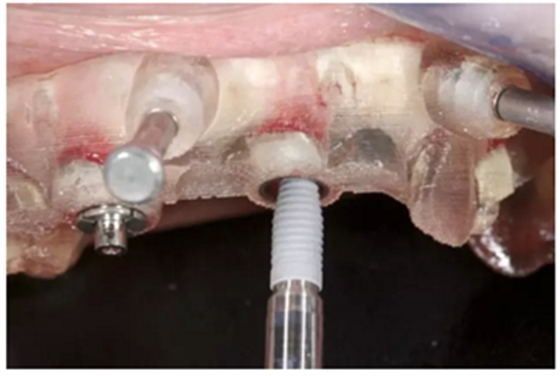

通過固位釘固定上頜NobelGuide外科導(dǎo)板和第一枚已植入的植體和導(dǎo)板基臺。

4枚NobelReplace CC RP4.3植體(11.5mm 軸向植體和13mm 傾斜植體)已植入完成:前牙區(qū)植體上裝配的是導(dǎo)板基臺,后牙傾斜植體上裝配的是內(nèi)錐形連接的引導(dǎo)式持釘器。

使用內(nèi)錐形連接引導(dǎo)式持釘器在下頜前牙區(qū)植入NobelReplace CC植體。

4枚NobelReplace CC植體均已植入完成:前牙區(qū)植入NP 3.5*13mm植體并裝配引導(dǎo)式基臺以固定導(dǎo)板,后牙區(qū)植入RP4.3*16mm植體并裝配內(nèi)錐形連接引導(dǎo)式持釘器。